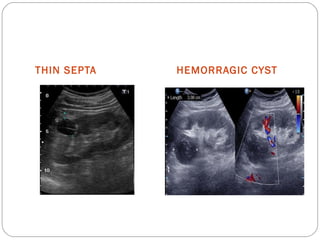

CATEGORY II



 Cysts complicated by prior infection or haemorrhage

 Benign cystic lesion with hairline thin septa

 Fine calcification in walls/ septa

 Atleast one fourth of the lesion’s circumference should extend outside the

kidney so that the smoothness of the wall can be evaluated

 Minimal perceived post contrast enhancement

 Non enhancing high attenuation (40-100 HU) lesion < 3 cm in diameter

THIN SEPTA HEMORRAGIC CYST